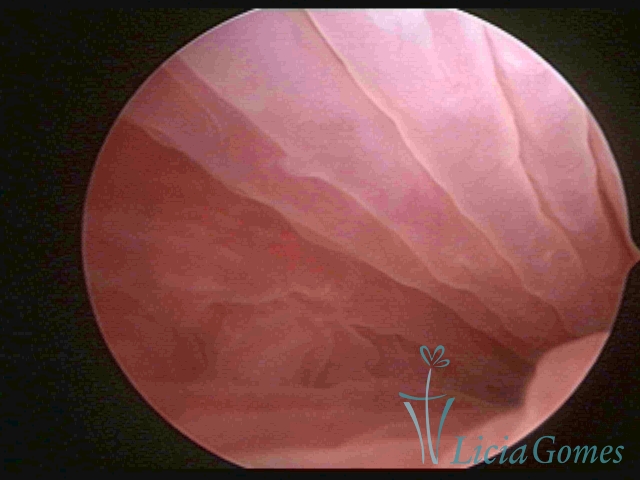

Segunda porção ou setor médio

No terço ou setor médio do canal cervical perdemos o detalhe das papilas, sendo possível a visualização de pregas e criptas. Normalmente observamos os sulcos longitudinais, que são os tecidos mais compactos, com a superfície mais vascularizada, cujos vasos seguem o seu trajeto.